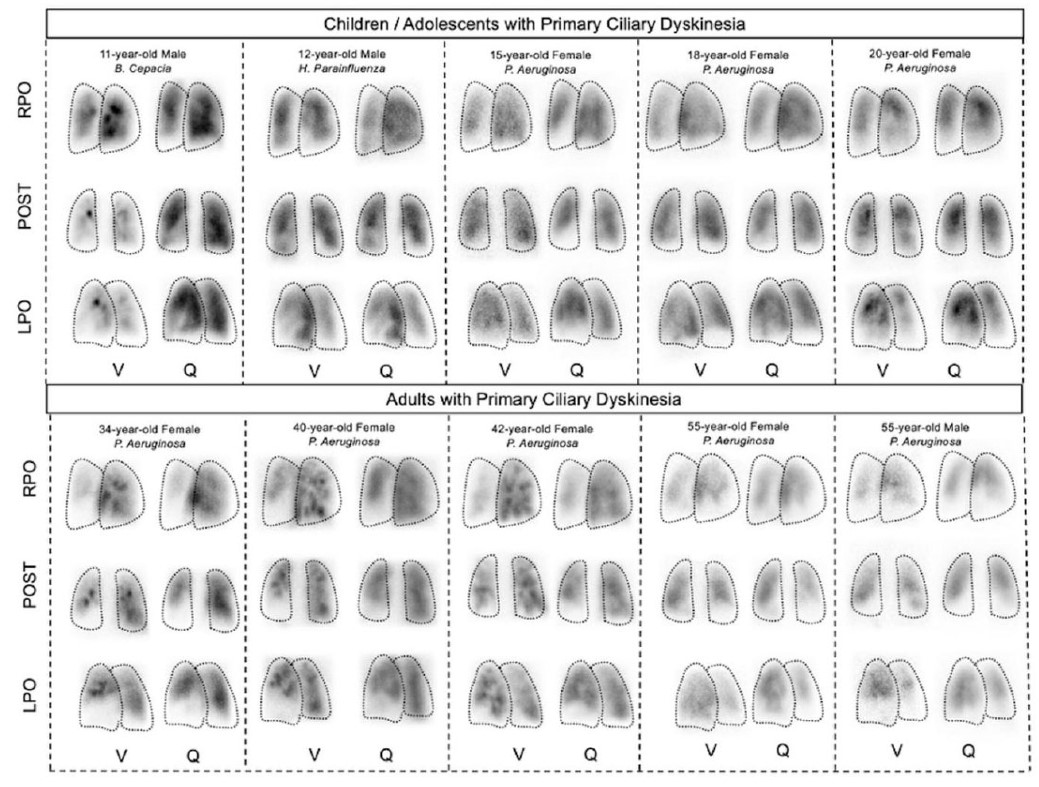

All patients with PCD demonstrated V/Q scans with mismatches (Fig. 2 ). Pediatric patients showed peripheral ventilation defects, with mostly preserved perfusion. Compared with children, adults showed pronounced mismatches. The extent of V/Q abnormalities increases with age, reductions in FEV 1 , and radiographic changes on chest CT scans.

Ventilation/perfusion (V/Q) scans in Pediatric and Adult Patients with Primary Ciliary Dyskinesia (PCD) carrying the homozygous RSPH4A [c.921+3_921+6delAAGT] genetic variant.

Representative planar V/Q scan images from children, adolescents, and adults with genetically confirmed PCD are shown in Anterior (ANT), Posterior (POST), Right Posterior Oblique (RPO), and Left Posterior Oblique (LPO) projections.